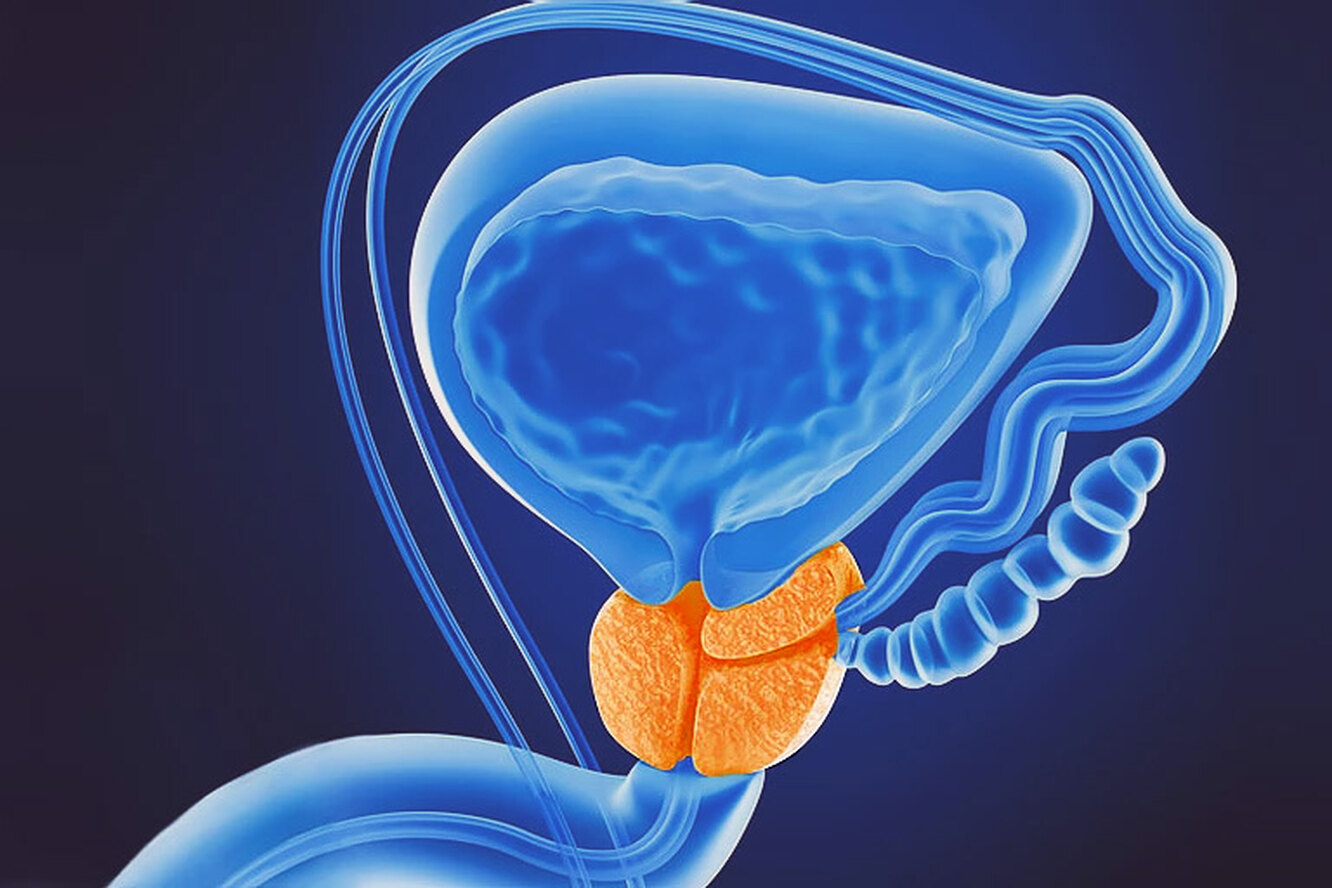

Простата, обычно ассоциируемая с мужским здоровьем после полового созревания, также присутствует у детей, хотя и в значительно меньших размерах. Этот орган, расположенный под мочевым пузырем и окружающий уретру, играет роль в выработке жидкости, которая составляет часть семенной жидкости. Несмотря на то, что проблемы с простатой у детей встречаются редко, понимание её развития и потенциальных патологий важно для ранней диагностики и лечения.